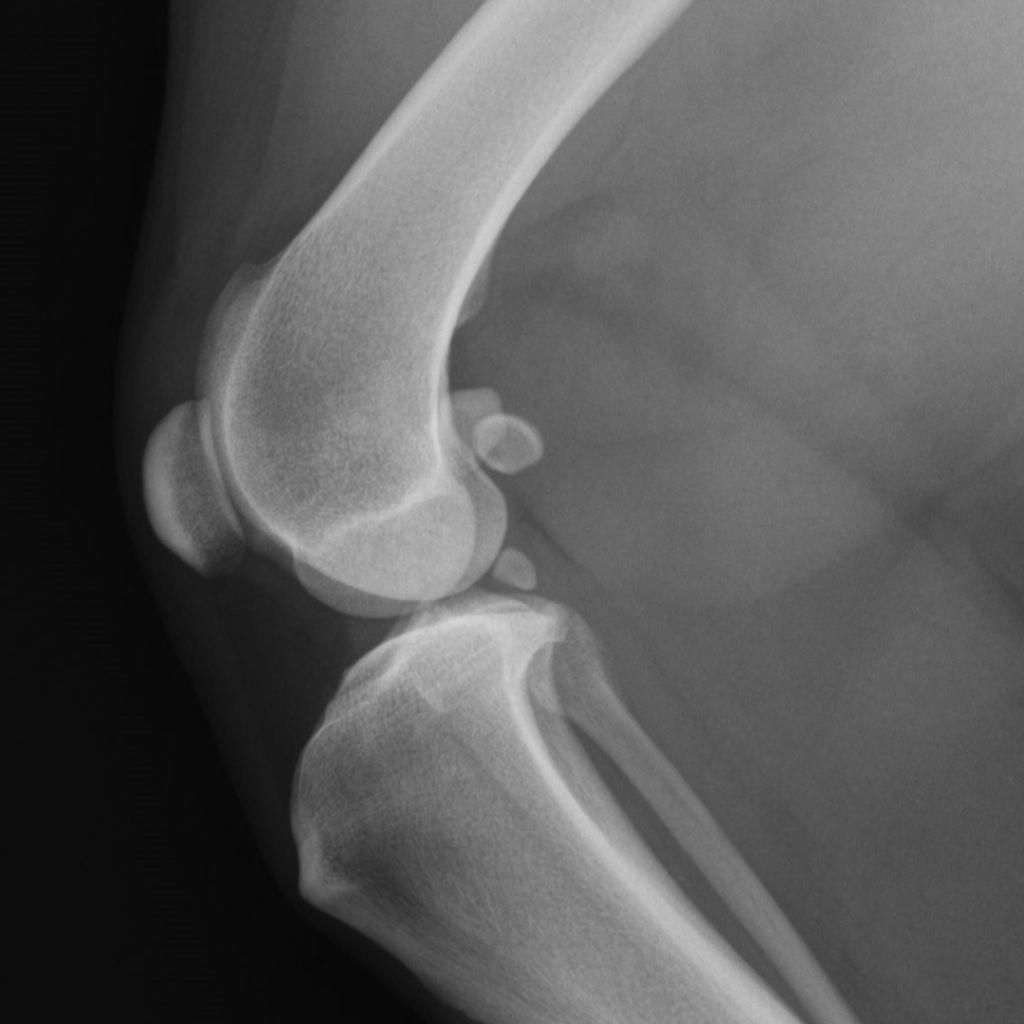

De patella (knieschijf) is een plat botje dat zich aan de voorkant van het kniegewricht bevindt. Het zit vast in de pees van de grote dijspier, die middenvoor aan het scheenbeen trekt. Zo kan de hond staan en springen. Om ervoor te zorgen dat de patella tijdens bewegingen binnen het gewricht blijft, heeft het gewricht een groef aan de voorkant. Hier past de knieschijf precies in. Tijdens het bewegen glijdt de knieschijf op en neer in deze groef. Aan de zijkanten wordt de knieschijf in de groef gehouden door het gewrichtskapsel en door uitlopers van de peesplaten van de spieren rond het gewricht.

Bij patella luxatie glijdt de knieschijf uit het gewricht. Als dat gebeurt hinkt de hond tijdens het lopen.